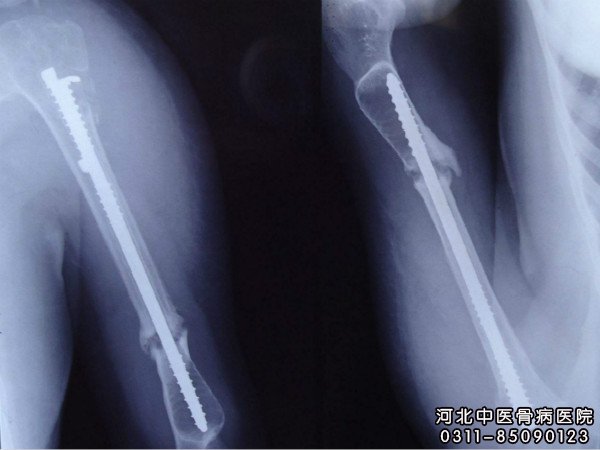

骨折在正常愈合所需的时间(一般为4个月内),仍未达到骨折完全愈合的标准,就可以定义为骨延迟连接。从x线显示 骨折端骨痂少,轻度脱钙,骨折线明显,但无骨硬化表现。对于骨不连和哪些因素有关呢?